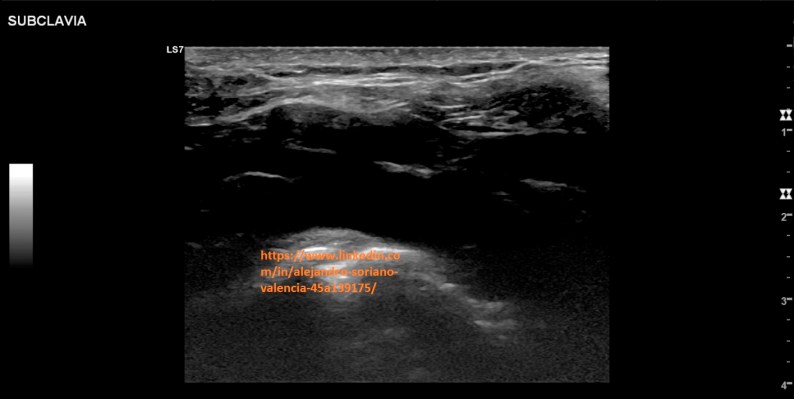

o Subclavia.

Generalmente su porción más proximal podremos estudiarla

de manera supraclavicular mientras que por su tercio medio y más distal,

Generally, its most proximal portion can be studied supraclavicularly, while its middle third and more distal

se hará infraclavicular. Es un vaso de muy difícil acceso, por lo no

seremos capaces de hacer cortes transversales y no podremos comprimir

adecuadamente.

3. Subclavia longitudinal.